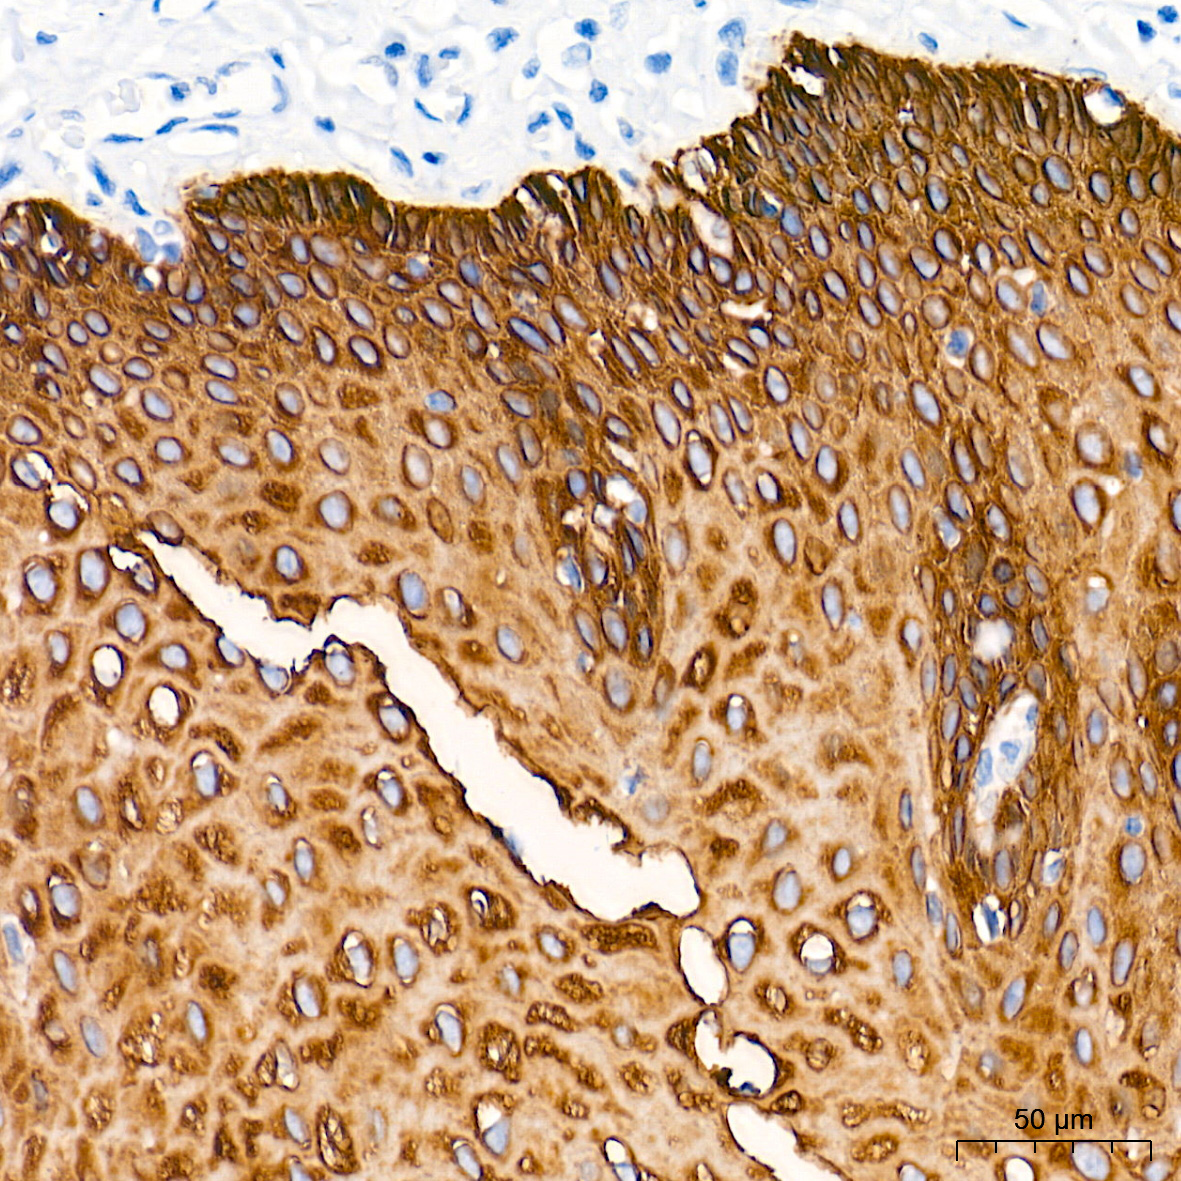

细胞骨架(Cytoskeleton)由微管(Microtubule)、微丝(Microfilament)及中间纤维(Intermediate filament)组成,是细胞器互作和细胞间交流的结构基础,在胚胎发育和机体稳态平衡的建立和维持等生理过程中发挥重要作用。微管主要由α及β微管蛋白组成,微管数量的减少是细胞恶性转化的重要标志。微丝主要由肌动蛋白(Actin)构成和肌球蛋白(Myosin)一起发挥作用,在肿瘤细胞内原有的微丝束明显减少甚至消失,常出现肌动蛋白凝聚小体。中间纤维常由波形蛋白(Vimentin)、角蛋白(Keratin)、结蛋白、神经元纤维、神经胶质纤维构成,在肿瘤中瘤细胞仍能基本保持其起源细胞的中间纤维类型,这有助于确定肿瘤组织的起源。细胞骨架信号会受到包括Rho家族以及它们的下游蛋白激酶效应器Rho激酶(ROCK)和p21活化激酶(PAK)的调控。